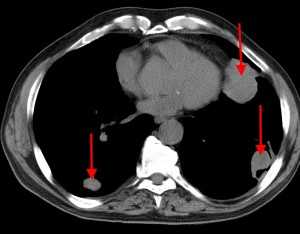

КТ: метастазы в легких при раке молочной железы. На изображении справа красной звездочкой отмечен опухолевый узел в молочной железе, красными стрелками - область прорастания опухоли в грудную стенку. Синими звездочками отмечен карциноматозный плеврит — скопление жидкости в плевральной полости. Слева стрелкой отмечен вторичный узел.